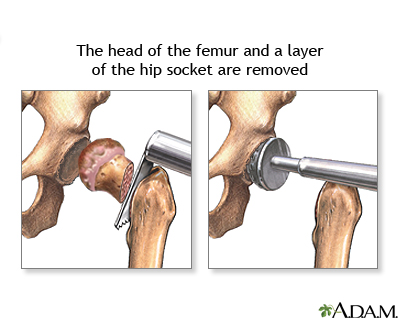

Замена таз сустава

Замена таз сустава 113 фотографий